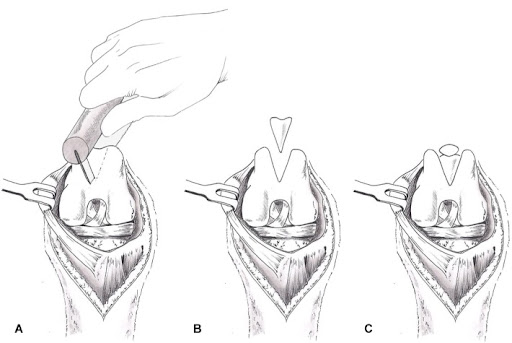

- Sulcoplasty

- Deepening of the groove where the patella normally sits in to create stability using either a block recession sulcoplasty or wedge recession sulcoplasty (Figure 4 and 5).

Figure 4: Block recession sulcoplasty (Veterinary instrumentation 2019, https://www.petvetbiomed.com/html5/web/10200/36779ImageFile3.pdf)

Figure 5: Wedge recession sulcoplasty (Dona et al. 2018, DOI: 10.2147/vmrr.s142545 )